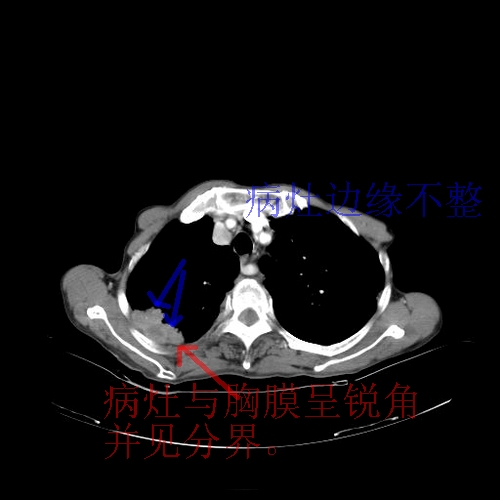

这个病人首先是胸部病变的定位到底是肺内还是肺外。仔细观察块影位于胸膜下,与胸膜间有透亮带,且近端血管未见明显推移而是引流样改变,形态分叶,说明这个病灶位于肺内胸膜下。很可能是腺癌,腺癌最易致颅内高密度转移灶。局部胸膜有侵犯。

8楼版主所提的问题横好:此病例的讨论焦点应该是\"病灶的位置\".我认为其实质是“局限性胸膜间皮瘤与肺内肿块的鉴别诊断!”

建议楼主提供强化的肺窗及双窗位图象{病灶边缘血管和支气管是否在病灶边缘突然中断换进入病灶内,如有可提示是肺内灶,如周围血管支气管有移位可提示是肺外病灶,如胸膜间皮瘤。胸膜间皮瘤的胸膜外脂肪层一般较清晰}。

本病灶定位是关键,我觉得从其特点分析,多考虑肺内病灶.首先应考率:肺内腺癌伴颅内转移伴出血